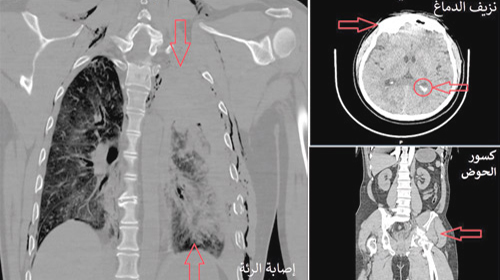

موضحاً بأنه بعد استقرار ضغط الدم لدى المريض تم إخضاعه للفحوصات الشعاعية بالأشعة العادية والتصوير المقطعي (C.T Scan) على منطقة الرأس والحوض والعمود الفقري، مشيراً إلى أن النتائج أبانت وجود نزيف داخل الجمجمة وآخر في الرئة ومنطقة الحوض، بالإضافة إلى حصر عدد 6 كسور في الضلوع الصدرية من جهة اليسار، وكذلك اتضح دخول هواء للمنطقة الواقعة بين جدار الصدر والرئة أو ما يعرف بالاسترواح الصدري الأمر الذي أدى إلى الضغط على الرئة.

وأشار الدكتور العسيري بأنه على الفور تم وضع خطة علاجية تقتضي بسرعة سحب الهواء داخل الصدر وإخضاع المريض لعملية جراحية دقيقة وكاملة استغرقت 4 ساعات تم فيها استخدام تقنيات حديثة تعرف بأسم (Video Assisted Thorciscope Surgery)، موضحاً أن هذه التقنية حددت بدقة الأوعية الدموية النازفة في منطقة الصدر وسرعة معالجتها، والتي كانت تمثل خطورة كبيرة على حياة المريض.